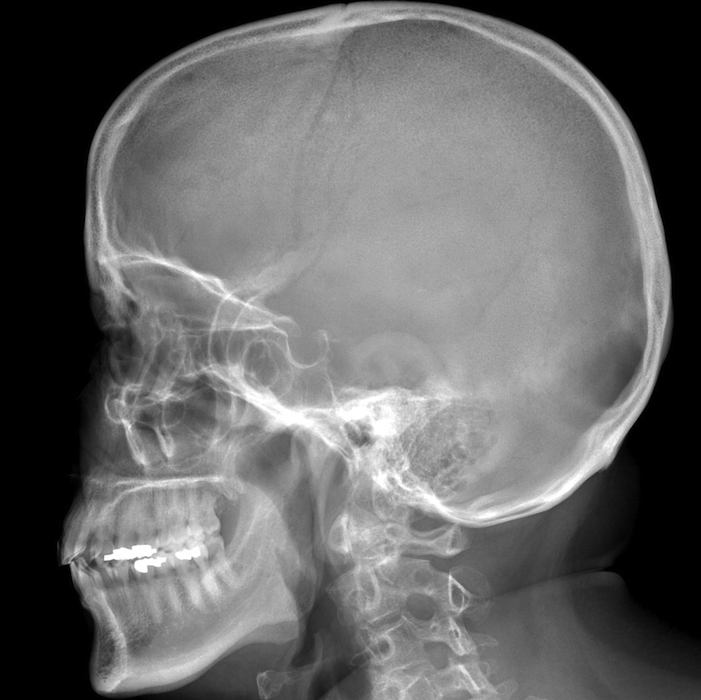

Figure 1 for case Paget disease ( RID3815 )

Figure 1

geographic lytic region in the occipital parietal and frontal bones in a paget's patient, may be compatible with osteoporosis circumspecta. most commonly in the frontal bone.

Paget disease ( RID3815 )